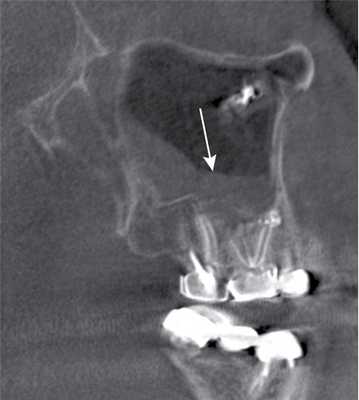

Воспалительные изменения слизистой оболочки верхнечелюстной пазухи, существующие в течение длительного времени, вовлекают в процесс костную стенку. На компьютерных томограммах отмечается утолщение костной стенки в костном режиме и появление «оптического эффекта» — уплотнение стенки в 1,5—3 раза за счет отека надкостницы — при просмотре в мягкотканом режиме (рис. 1, а, б) [9]. При одностороннем процессе, характерном для одонтогенного поражения, на контралатеральной интактной стороне такого эффекта не определяется.

Рис. 1. Рентгеновская компьютерная томограмма околоносовых пазух. Коронарная проекция: мягкотканное окно (а) и костное окно (б).

В костном режиме программы просмотра изображений утолщение костных стенок верхнечелюстной пазухи определялось в 21% случаев (рис. 2, 3), что указывает на хронический характер воспаления. «Оптический эффект» в мягкотканном режиме программы просмотра диагностических изображений определялся у 30,7% больных, что указывает на вовлечение надкостницы.

При воспалительных изменениях в ретроантральной жировой клетчатке верхнечелюстной пазухи на РКТ повышаются денситометрические значения ее плотности [10]. При одностороннем процессе отмечается выраженная асимметричность значений плотностей (рис. 4).

Рис. 4. Рентгеновская компьютерная томограмма околоносовых пазух. Аксиальная проекция, костное окно.

В 63,2% случаев на РКТ при выявлении одонтогенного верхнечелюстного синусита отмечалось уплотнение жировой клетчатки. Исследователи связывают это с переходом воспалительной инфильтрации пристеночной слизистой по периваскулярным пространствам к ретромаксиллярной клетчатке [7, 11, 12].